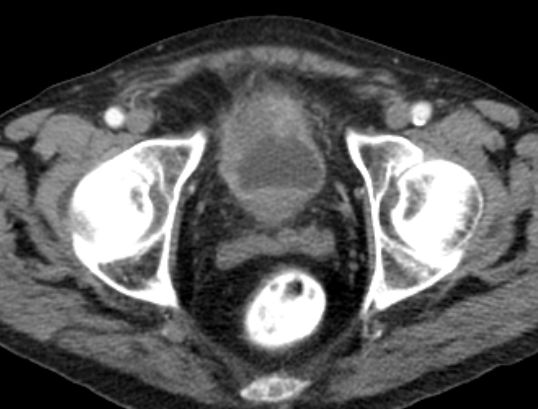

| Becken-Rezidiv | 54-jährige Frau nach radikaler Zystektomie und Anlage eines Ileumconduits wegen eines Plattenepithelkarzinoms der Harnblase vor 8 Monaten. Jetzt Verdacht eines Abszesses an der linken Beckenwand. Anlage eines Transversostomas und Drainage, später transvaginale Drainageeinlage. Jetzt Tumorfreilegung, Nekroseausräumung, Drainage. Histologie: Plattenepithelkarzinom. Destruktion des Beckenknochens links mit Einbruch ins Acetabulums. | ||